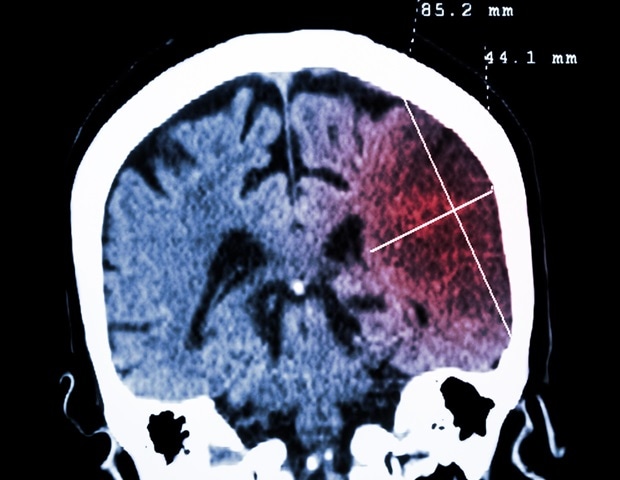

"Deterioration in the structure or function of nerve cells (neurodegeneration) begins many years before any symptoms become obvious. This means that diagnosis often occurs at a relatively late stage in the disease course, when substantial damage to nerve cells has already taken place," explained Dr Alastair Noyce, from Queen Mary University of London and Co-chair of the author group.

Neurodegenerative diseases are becoming more common as people live longer, but they are not an inevitable consequence of normal ageing. Worldwide, Alzheimer's disease affects about 50 million people and Parkinson's disease affects more than 6.1 million people; these numbers are rising.